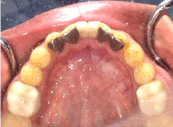

A 19 years old male patient reported with the chief complaint of missing anterior teeth in the mandibular anterior region and need for aesthetic restoration of the same with fixed dental prosthesis. He was wearing mandibular anterior removable partial denture from last 10 months. The patient gave the history of extraction due to trauma of mandibular central incisors one year back. His expectations were reasonable and his psychological profile was good. Intra oral examination revealed missing mandibular central incisors with a slight buccal defect in the gingiva in the anterior region of tooth #31 and #41 due to pressure exerted from wearing the removable partial denture from last 10 months (Figure 1). Replacement of the missing teeth with implant needed bone augmentation procedure to allow for optimal bone integration and stability of the implants. The patient did not agree to the proposed surgical treatment plan. Also on clinical and radiographic examination, the teeth demonstrated gingival margins much coronal to the cement-enamel junctions, and large pulp chambers. A conservative and minimally invasive adhesive bridge was planned to restore the missing mandibular central incisors. Diagnostic wax up was performed to achieve the final outcome of the fixed restoration (Figure 2).

Figure 1. Intra oral view with missing mandibular central incisors.